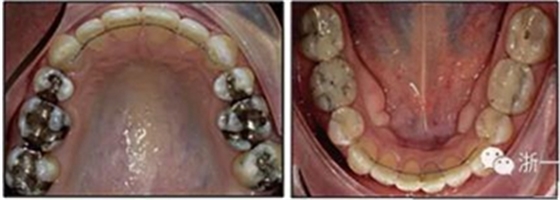

患者曾行正畸治療,現(xiàn)覺(jué)笑容不美觀前來(lái)就診?;颊哒嬗^及側(cè)貌示下頜發(fā)育不足,偏高角,唇閉合不全。上下頜中線(xiàn)齊。覆合、覆蓋4毫米。磨牙關(guān)系及尖牙關(guān)系II類(lèi)。上頜擁擠度4mm,下頜擁擠度6mm。4顆第一前磨牙在第一次正畸治療時(shí)已拔除。上下牙弓呈尖圓型,牙弓狹窄。

患者側(cè)貌改善,下唇唇肌緊張消失,上下唇可自然閉合。磨牙及尖牙關(guān)系糾正至I類(lèi),覆合覆蓋正常。上下頜弓型糾正至卵圓形,牙弓寬度增加。頭影測(cè)量分析示SNA角81.8°,ANB角3°。頭影測(cè)量重疊圖示下頜骨向后旋轉(zhuǎn),垂直面高度略有增加。